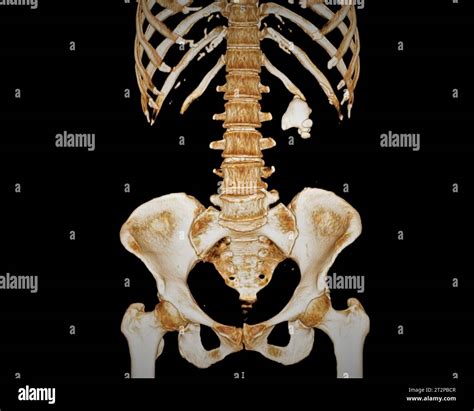

KUB X-Ray

A KUB (Kidney, Ureter, and Bladder) X-ray is a basic imaging test that can sometimes visualize certain types of kidney stones (specifically calcium-based stones). However, it is not very sensitive and often fails to detect small stones or stones hidden behind bowel gas or bones. It is sometimes used to track the progress of a known stone over time.